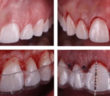

POINT DE CONTACT INTERPROXIMAL EN ZONE ESTHÉTIQUE POINT DE CONTACT INTERPROXIMAL ET ESTHÉTIQUE GINGIVALE EN SECTEUR ANTÉRIEUR L’esthétique gingivale en…

ET SI L A PHOTO DEVENAIT NOTRE MEILLEUR OUTIL CLINIQUE ?

INTRODUCTION : PHOTOGRAPHIER, UN ACTE CLINIQUE À PART ENTIÈRE La photographie a longtemps été perçue comme une activité annexe à…